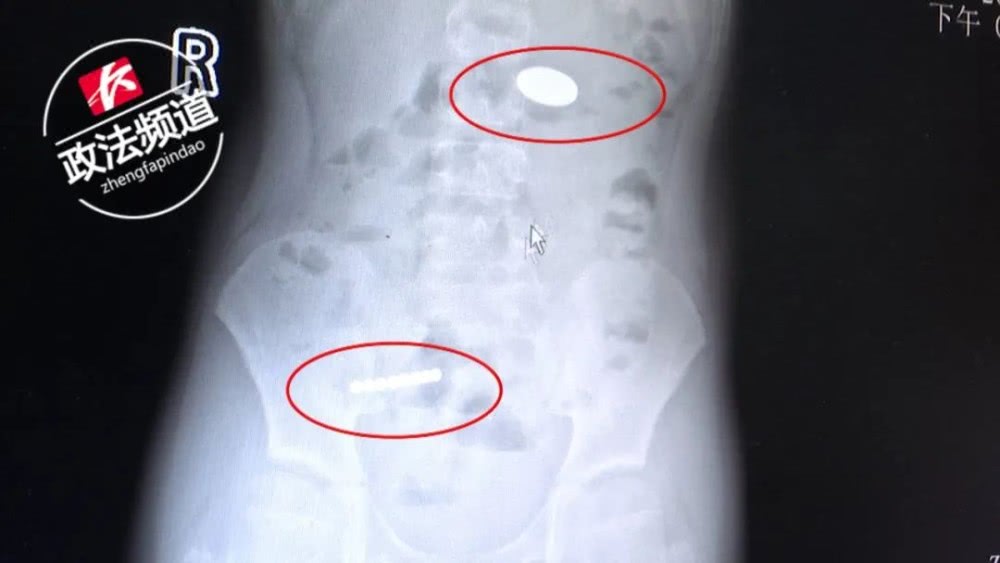

从X线检查结果可以看到

小明右下腹有八颗珠子连在一起,

左上腹还有一枚圆形的物体,好像是硬币。

医生紧急为他进行处理,

通过手术将这些“小玩意儿”取了出来。

通过小明后续采访,我们得知,

肚子里的珠子,就是在小卖部里面常见的磁珠,

小明一边玩一边玩就吞下去了,

后来吞硬币是为了把磁珠“吸”出来。